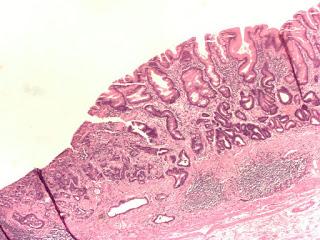

Adénocarcinome gastrique à différenciation cellulaire faible à modérée (…), présence d’une métaplasie intestinale importante – caractérisée par la présence de cellules calciformes (considérée comme un facteur de risque pour le développement d’un adénocarcinome) avec en outre la présence d’épithélium fovéolaire. L’antre gastrique (…) est visible : projections digitales dans l’intestin.

Source iconographique : https://commons.wikimedia.org/wiki/File:Gastric_adenocarcinoma.jpg